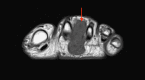

Phosphaturic mesenchymal tumors (PMT) are a rare neoplasm oftentimes associated with tumor-induced osteomalacia (TIO). The non-specific presentation and symptoms of these pathologies make them difficult to diagnose. We report a case of a 52-year-old patient with an intermetatarsal phosphaturic mesenchymal tumor who presented to the orthopedic sports medicine clinic with metabolic deficiencies and bilateral subtrochanteric cortical stress fractures indicative of osteomalacia. The tumor was entirely resected within nine months of symptom onset and has shown no recurrence at the one-year follow-up. This case report characterizes an unusual cause of stress fractures presenting to orthopedic sports medicine clinics and the variability in the presentation of phosphaturic mesenchymal tumors.